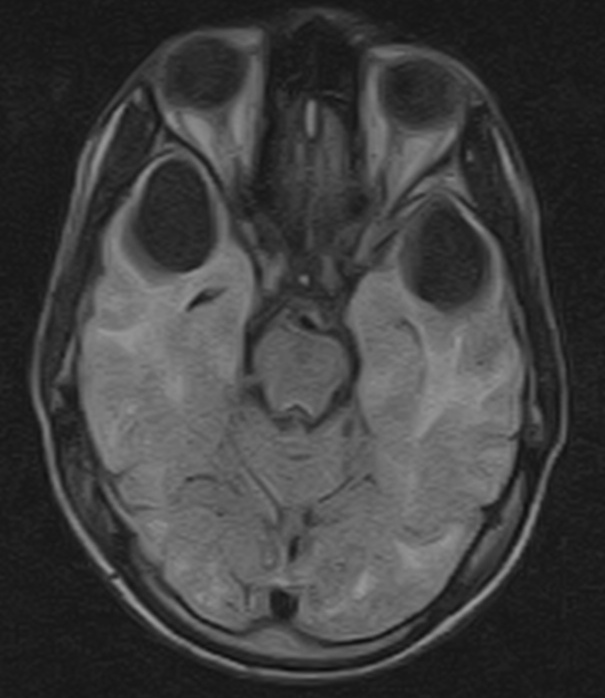

Figure 2 from Canavan disease CT and MR imaging of the brain

Figure 2 from Canavan disease CT and MR imaging of the brain Radiology Van Syndrome It is named after the two doctors who first described the disease, and affects. vhl is a rare disorder caused by a faulty gene. The growth of cysts or tumors. the authors provide an updated review of the molecular cytogenetics and clinical features of. Radiology Van Syndrome.